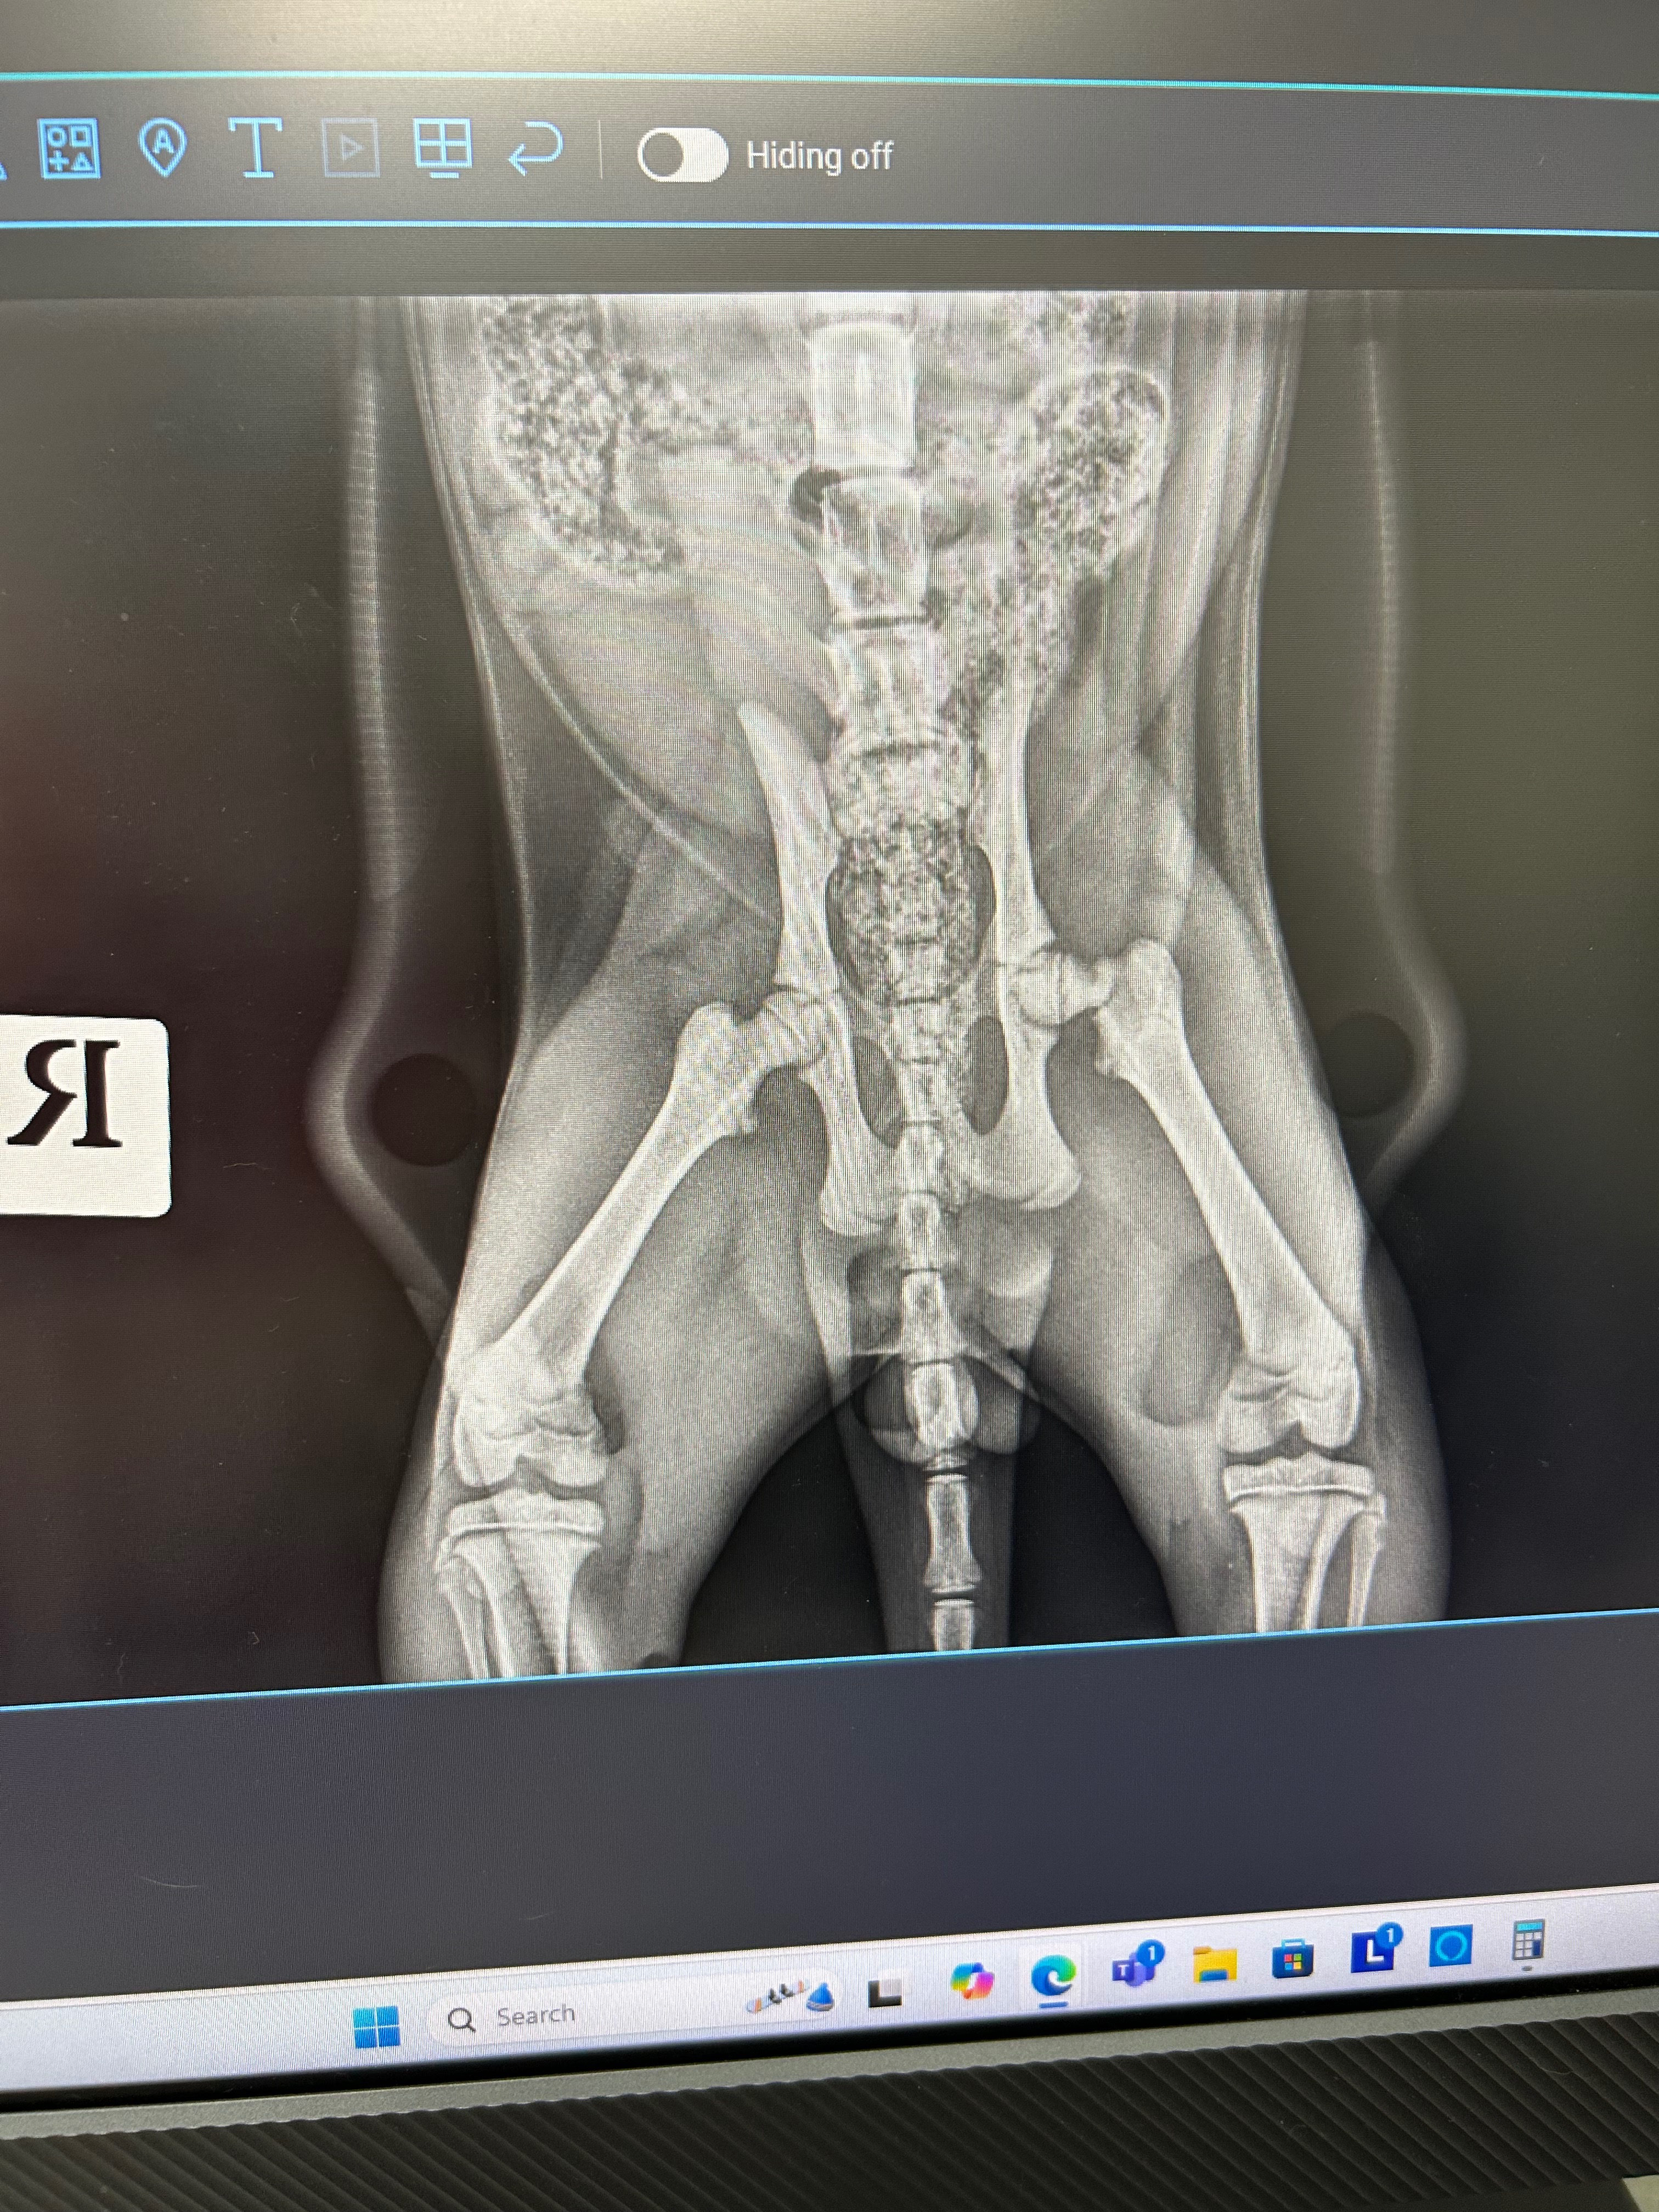

Toby’s x-ray determined that unfortunately he will need his leg amputated. Whilst this is very difficult to come to terms with, it does lessen the cost of the surgery and increases the likelihood of him staying with us instead of him being surrendered. Currently we have raised $1,418, words cannot express how truly grateful and thankful we are for everyone who has donated and shared our gofundme. Toby’s leg amputation is going to cost a total of $2,600, this needs to be done sooner rather than later to avoid complications such as his muscles hardening, loss of blood flow to his leg leading it to deteriorate and post op infection.

Hi, my name is Sasha. Today our cat Toby got into an unfortunate accident, he has a broken leg and possibly a broken hip as well. He has been to the vet, had some pain relief and is coming home with us for the night, however, due to financial hardship we face the very heartbreaking and difficult decision of surrendering him in order for Toby to receive the care he needs and deserves. This is our last and only option to potentially keep Toby in his family home. I have 3 little girls who absolutely adore him, as do I. Toby has been an emotional support animal for not only myself but my children and our home wouldn’t be the same without him in it. Please, if you can, help us by donating. Any amount will help and we would be forever grateful. The goal is $3,500, this includes more medication, x ray’s, and surgery where he may or may not lose his leg. If the goal isn’t met in a few days, I will happily reimburse each and everyone one of you who donated so please, if you able to donate don’t do it anonymously.